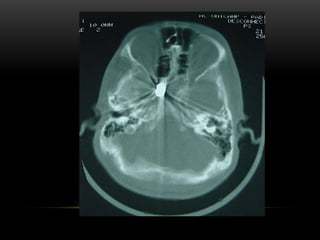

A TC é um tipo especial de procedimento com raios X

que envolve a medição da atenuação dos raios x.

 A maioria dos cortes de TC são axiais ou transversais.

 Para cada fatia, o tubo de radiação gira em torno do

paciente para obter uma espessura de corte pré-

selecionada.

A maioria dos sistemas de TC emprega o desenho de

rotação contínua e “feixe em leque”.

O QUE ÉTOMOGRAFIA ( TC) • A TC é um tipo especial de procedimento com raios X que envolve a medição da atenuação dos raios x.  A maioria dos cortes de TC são axiais ou transversais.  Para cada fatia, o tubo de radiação gira em torno do paciente para obter uma espessura de corte pré- selecionada. A maioria dos sistemas de TC emprega o desenho de rotação contínua e “feixe em leque”. •